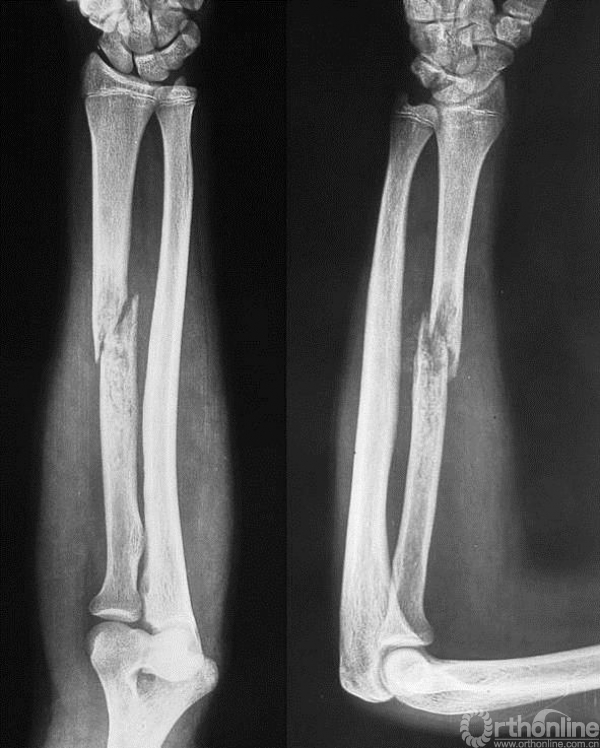

男性,16岁。患者入院3个月前摔伤右前臂,即出现疼痛、肿胀、活动受限。

图14-1 伤后X线平片正侧位

1.有外伤病史,但无骨折前局部疼痛等症状。而是在低暴力创伤的情况下出现骨折,可能并非单纯创伤暴力所致。

2.X线平片显示右桡骨干骨皮质不连续,骨折端内可见边界不清之溶骨破坏,其内密度不均,应该首先考虑为病理骨折,但又未见明确的骨膜反应和软组织包块。所以应继续进行检查,包括细致的影像学检查如局部加强CT来判断是否确为病理骨折、是否有皮质破坏及软组织包块。